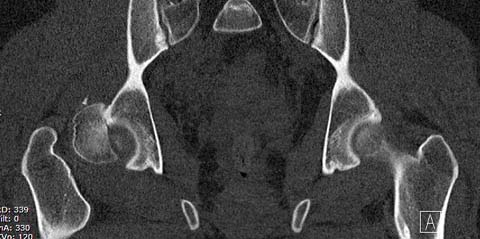

Уважаемые коллеги добрый вечер! Хотелось бы узнать ваше мнение о возможных ранних сроках наступления асептического некроза или коксартроза при данном виде оперативного лечения, может кто-то уже оперировал данную патологию и есть наблюдения. Случай практически идентичный описанный в январе 2015 на ортофоруме Никитой Николаевичем Заднепровским. Молодой человек 20 лет ДТП 23.02.2015, Диагноз: Сочетанная травма. Закрытый переломо-вывих головки и перелом заднего края вертлужной впадины (Pipkin4) правой бедренной кости. Открытый подтаранный вывих правой стопы. При поступлении в ЦРБ вправление вывиха головки бедра и подтаранного вывиха стопы.

Далее перевод к нам в Травмоцентр и 03.03.2015. через 8 дней операция, выполнен остеосинтез головки 3-мя самокомпрессирующими винтами Autofix под разными углами с погружением в субхондральный слой. Доступ Kocher-Langenbeck с флип-остеотомией большого вертела и задним хирургическим вывихом головки бедра. В полости сустава два свободно-лежачих фрагмента хряща головки, которые были удалены. На снимках виден дефект хряща головки после репозиции. Небольшой фрагмент заднего края фиксирован двумя спонгиозными винтами. Далее шов раны с дренированием. На 2 сутки пациент поворачивался на здоровый бок с валиком между ног, на 4 сутки сидел в кровати и на 6 сутки ходил с помощью костылей.

КТ после вправления - это последнее?

На мой взгляд, развитие артроза и AVN в большей степени зависит от давности вывиха и качества оперативной техники. Хирургический вывих бедра- не самая простая процедура и с подводными камнями, в остеосинтезе из переднего доступа тоже есть проблемы.

Здесь значимый задний край с подвывихом бедра кзади и острым краем вертлуги - задний доступ с вывихом и синтезом заднего края винтами и пластиной